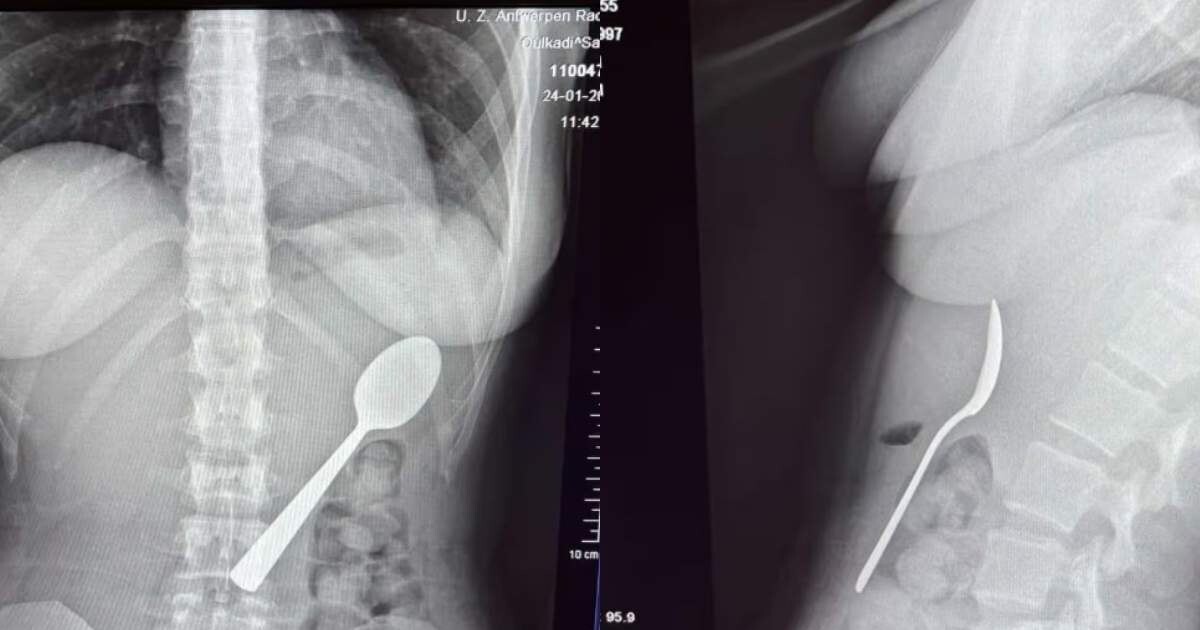

O tânără a înghițit o lingură de 17 cm din cauza câinelui: „Fie înghițeam, fie mă sufocam”

O femeie de 28 de ani din Belgia a trăit momente terifiante după ce a înghițit accidental o lingură de 17 centimetri. Incidentul s-a produs în timp ce mânca iaurt pe canapea, iar totul a pornit de la o reacție neașteptată a câinelui ei, un energic Hungarian Vizsla pe nume Marley.

Medicii au decis să îi îndepărteze lingura sub anestezie locală, evitând o operație deschisă. Procedura a fost delicată , necesitând rotirea lingurii în interiorul stomacului pentru a putea fi extrasă în siguranță.